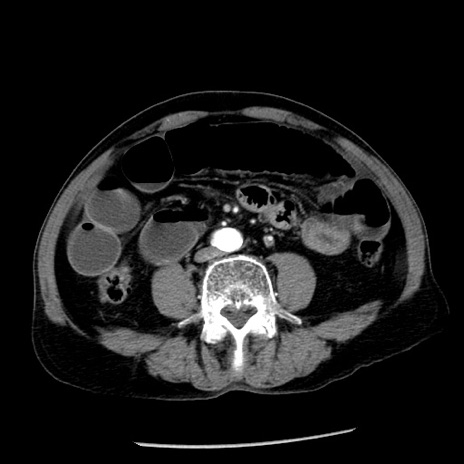

冠状断像

【症例】80歳代男性

【主訴】嘔吐

【現病歴】昨晩2回嘔吐あり、今朝になっても嘔吐あり。来院。

【既往歴】胃潰瘍

【身体所見】意識清明、BT 37.6℃、BP 166/95mmHg、HR 100bpm、SpO2 97%、腹部:平坦・軟、腸蠕動音聴取良好、圧痛なし。

【データ】WBC 21900、CRP 1.46